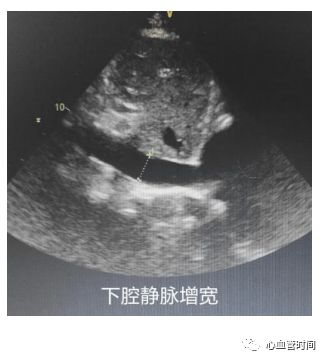

剑突下切面

对于一些胸前切面显示不清的患者,剑突下切面可以很好地 作以补充。 房间隔 在患者成像条件良好的前提下,剑突下切面是观察 房间隔缺损的绝佳切面。该切面房间隔相对垂直于探头,可更好的显示 过隔血流,像卵圆孔未闭的几毫米的血流也能轻松显示,且可更好的与腔静脉的血流做区分,明确血流来源。 下腔静脉

有无增宽、有无正常塌陷,对于怀疑

肺栓塞

的患者还要注意

下腔血流是否瘀滞

、是否有

血栓占位

。

下腔静脉

有无增宽、有无正常塌陷,对于怀疑

肺栓塞

的患者还要注意

下腔血流是否瘀滞

、是否有

血栓占位

。